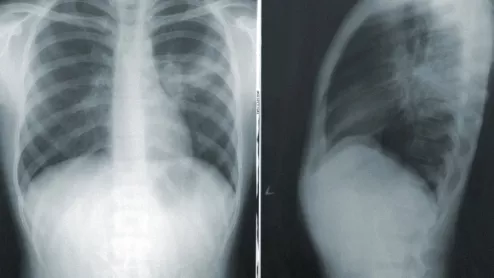

Chest X-ray. Using an explainable artificial intelligence (AI) model, researchers were recently able to accomplish highly accurate labeling on large datasets of publicly available chest radiograph X-rays..